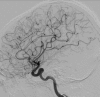

Figure 2

Figure 2. Digital angiography 30 hours after symptoms onset: normal.